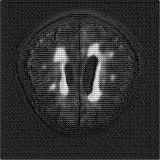

We obtain a subject-wise mean Dice score of 63.67% for the brain tumor segmentation. Utilizing a simple post-processing scheme of erosion and dilation with filter, we improve our mean Dice score to 68.01%. Figure 4 shows samples generated by our ASC-Net and Table 2 shows our before and after post-processing results. We attempted to apply f-AnoGANs [34] by following their online instructions and failed to generate good reconstructions as shown in Figure 5. The failure of AnoGANs in the reconstruction brings to light the issue with the regeneration based methods and the complexity and stability of GAN-based image reconstruction.